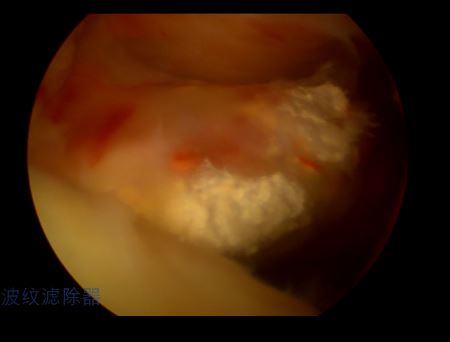

关节镜可以看见钙化灶有不同的表现,并在不同肌腱位置出现,手术中应该仔细寻找病变位置!

关节镜下钙化灶为石灰粉样、牙膏样

牙膏样钙化灶